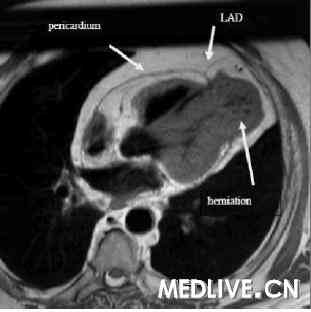

我们用一个带6个元件相控阵列线圈的1.5T的MRI扫描器。通过使用一种稳态梯度回波技术获取标准视图的电影回放,实施标准的心室功能检查。在心脏轴位和短轴平面用屏住呼吸的T1加权快速自旋回波MRI检查心脏和心包形态,并且在静脉给予钆对比剂后10分钟获取对比增强图像。MRI显示心尖处的心包缺如以及双心室尖部疝(图2和3),这些发现引导我们(将该患者)诊断为部分性CAP,LAD中部远端狭窄通过心包环来解释。用MRI完全确定CAP,用心室尖部疝解释LAD受压,以及已被证明的缺血导致了外科干预(图4A和4B)。在左乳内动脉成功地实施了心包成形术联合LAD旁路。术后即时MRI显示与心包成形术相关的心尖部运动明显改善。对照冠状动脉造影显示左乳内动脉通透性良好,LAD变形部分消失(图5)。该患者经过1年随访后目前没有(发生不良)事件。

图2. 心脏轴位T1 MRI显示左心包的部分性缺损 |

图3B. MRI显示双心室尖部疝 |